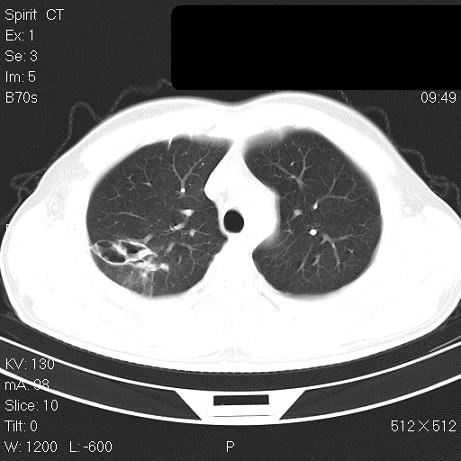

标题: CT7171B:补充治疗后2周复查 [打印本页]

标题: CT7171B:补充治疗后2周复查

治疗后2周复查,请讨论

结合以前的ct片,还是考虑肺挫伤,吸收多了。

支持:创伤性湿肺。现肺挫裂伤(出血 积气)大部分吸收。建议继续治疗!

结合以前的ct片,支持创伤性湿肺。现大部分吸收。

支持:创伤性湿肺、肺挫裂伤。现肺挫裂伤(出血、渗出、液气腔)大部分吸收。建议继续治疗!

支持:创伤性湿肺、肺挫裂伤。现肺挫裂伤(出血、渗出、液气腔)大部分吸收.

经治疗后病灶明显吸收,考虑创伤性湿肺、肺挫裂伤